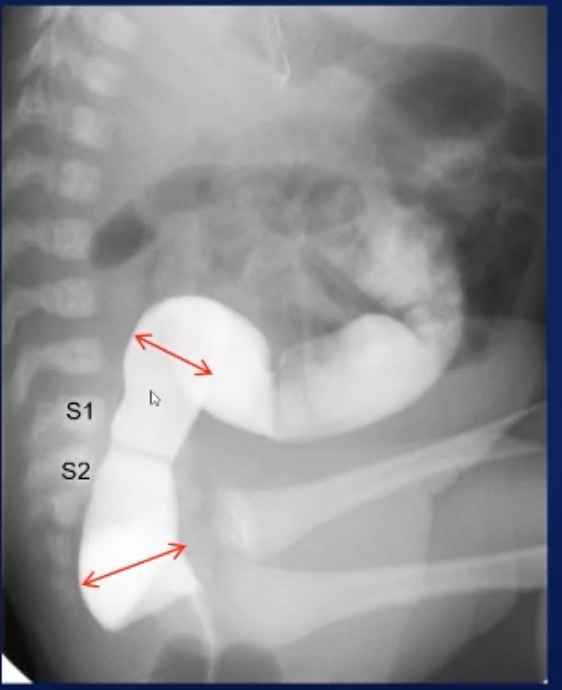

Contrast Enema

• Pediatric

• On lateral will see rectosigmoid junction at about S1-S2 and therefore would want to get a measurement on lateral view above and below this level to compare the recto-sigmoid ratio

• All spot fluoro, not exposure, not sine

• Start lateral and get rectosigmoid filling

• Watch colon fill

• Get RPO for splenic flexure (LUQ) and LPO for hepatic flexure (RUQ)

• Need reflux into TI/small bowel